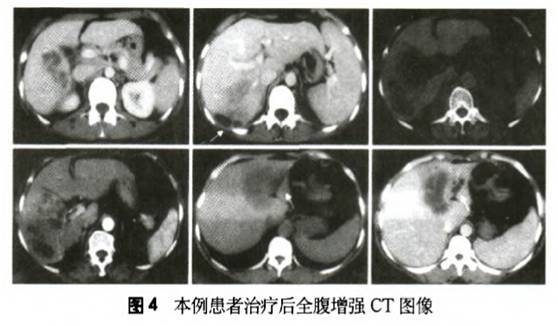

予吡喹酮治疗,按25 mg·kg-1·d-1,分3次口服,连服7 d,间隔1周后再服用第二个疗程,3个疗程后患者上腹部不适症状消失,复查血常规:E0%2。6%,肝功恢复正常,全腹增强CT示:病灶明显吸收,见图3。

本例患者虽未进食过生的或不熟的鱼、蟹等食物,但居住在肺吸虫病发病率较高区域,血中嗜酸性粒细胞比例明显升高,仔细观察其CT表现,肝右叶和左叶内病灶为多发囊状、分叶状低密度影,囊腔内无强化,囊壁强化,符合Kim等、Rha等和王小鹏报道的肝肺吸虫病的影像学特点(图4)。